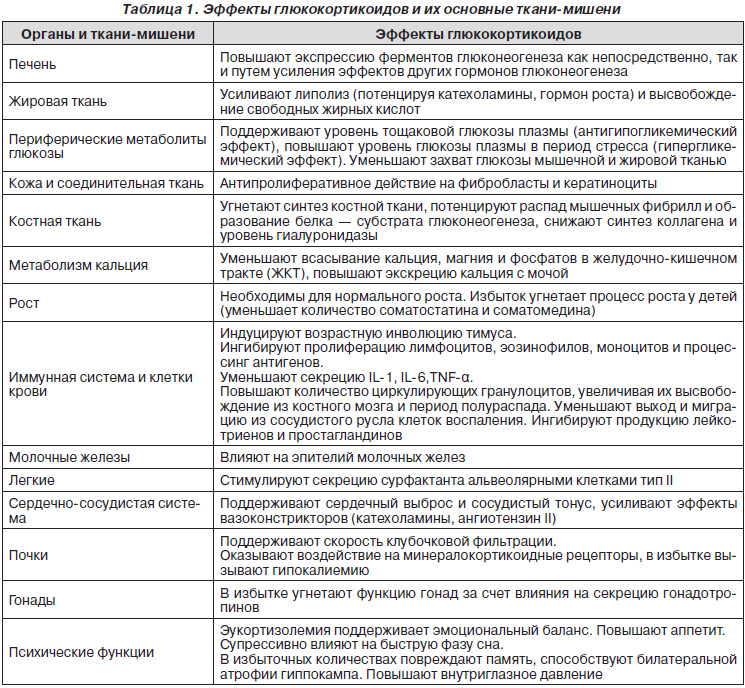

Основным глюкокортикоидом у человека является кортизол, избыток или недостаток которого сопровождаются угрожающими жизни сдвигами (табл. 1). В регуляции секреции кортизола принимают участие по меньшей мере 4 механизма, регулирующих функцию гипоталамо-гипофизарной системы: циркадный, стресс, принцип обратной связи, стимуляция цитокинами.